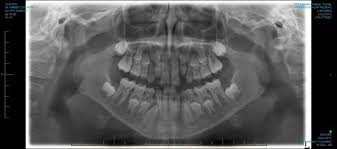

Dentaltown Boy 9 Years Old Referred For Panorex X Ray Due To Unerupted First Molar A Complex Odontoma Also Cal Dental Hygiene School Dental Humor Dentistry